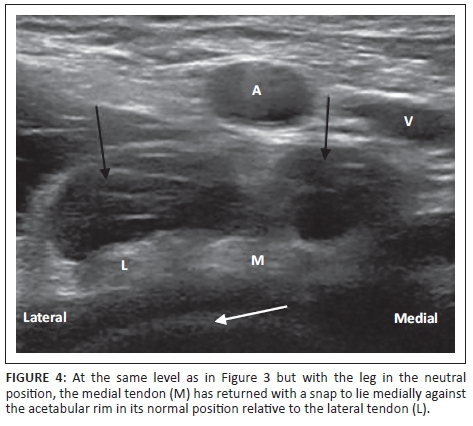

The femoro-acetabular morphology was normal. A dynamic ultrasound of the iliopsoas tendon was performed at the same appointment with an audible snap occurring whilst the patient returned the leg from flexion, abduction and external rotation or the frog-leg position (Figure 3) to neutral (Figure 4). The snap occurred as the medial component of the bifid tendon (which had rolled laterally over the lateral component during the frog-leg manoeuvre) returned abruptly over the lateral component to its original position, striking the superior pubic ramus. The referring surgeon elected to treat the patient conservatively with a bupivicaine and steroid injection under the bifid iliopsoas tendon, that produced symptomatic relief.